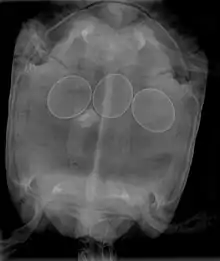

In reptiles, it is inadvisable to attempt to break a reptile egg to remove it from an egg-bound female. This procedure may be done by a veterinarian, who will insert a needle into the egg, and withdraw the contents with a syringe, allowing the egg to collapse and be removed. Non-surgical interventions include administering oxytocin to improve contractions and allow the egg(s) to pass normally. In many cases, egg-bound reptiles must undergo surgery to have stuck eggs removed.

Egg binding in reptiles is quickly fatal if left untreated; therefore, gravid females who become very lethargic and cease feeding need immediate medical treatment in order to treat the potentially life-threatening condition.